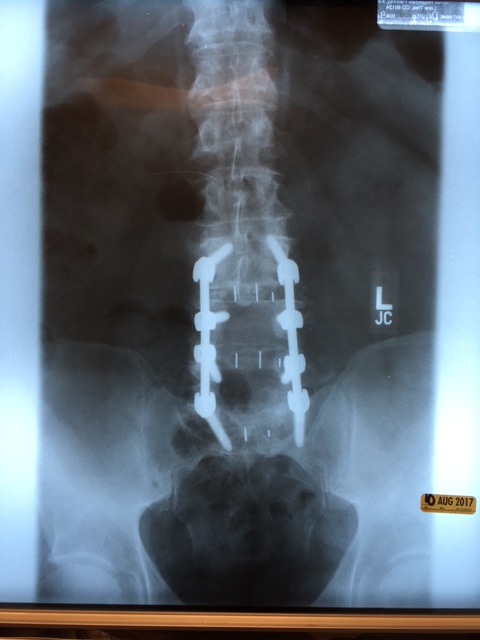

So once the spine surgeon got to see the MRI it proceeded almost as an emergency. I don’t know how they did it but we got the insurance approval and I was in for surgery 6 days later. It was about a 5 hour procedure because of how much had to be done. They removed the discs from L3 to S1 (what there was left of them) put in spacers, fused 4 vertebrae, cleaned our the vertebrae so the nerves could move and quit being crushed and then tied the whole thing together with two Titanium/Cobalt rods with 8 bolts. Here’s what it looks like: (I post these so the folks that like to diminish the seriousness of someone else’s issues can get a little squeamish. Also, its for those who love to tell you, “Oh that’s nothing!” My wife’s cousin from Frog Balls Arkansas had it WAY worse than that”, can seriously jump off a cliff.

This is 7 inches long:

The surgical PA said that they put in heavy duty rods and bolts because this is a typical rancher type injury and they knew that I’d be back at it. I have been doing the recovery by the book though so save the “don’t over due it” lectures. I CANNOT go through this again and the most important part of the recovery is getting a good solid fusion. Yesterday makes the 5th week since surgery and the recovery guides say that by 6 weeks the fusion should be well in hand but it needs at least 3 months to get strong enough for regular activity. So I am under orders to engage in no BLT’s: Bending (try putting on socks or wipe! TMI). Lifting (nothing over 10 pounds) or Twisting. I have all manner of gizmos to help me do everything. I use a gripper to get things off the floor, a gizmo for the bathroom, a shoe horn with an extension handle, elastic, no tie, shoe strings, a thing to help me put on socks, a walker, and my ever present hiking poles.

Once my son was done with school he came out and just lent a hand where needed. He has a very big heart and just having him around was comforting. The day I first saw the X-Rays, I had a pretty serious mental melt down. All I could think was that I was Frankenstein’s spawn. He was there and after having been through his own issues over the years, he had an insight that, I don’t think, anyone else could appreciate.